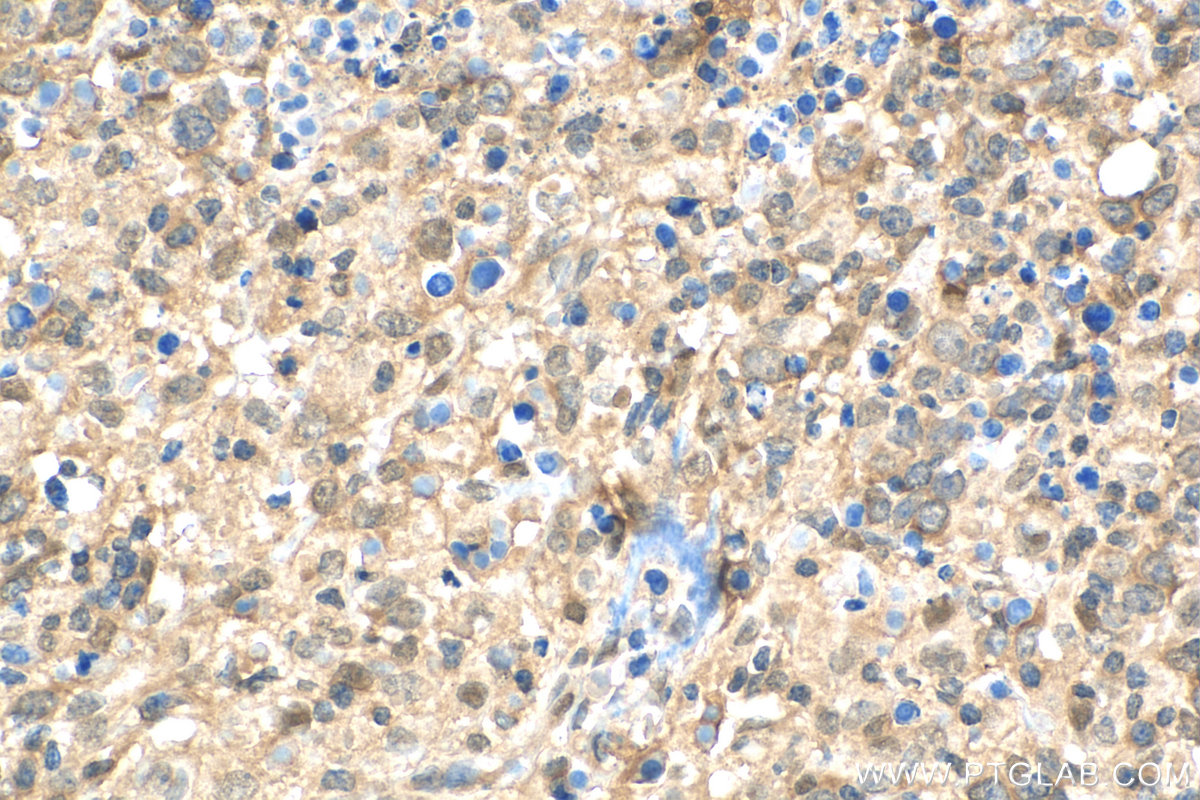

| Positive IHC detected in | human colon cancer tissue, human lymphoma tissue Note: suggested antigen retrieval with TE buffer pH 9.0; (*) Alternatively, antigen retrieval may be performed with citrate buffer pH 6.0 |

| Immunohistochemistry (IHC) | IHC : 1:50-1:500 |